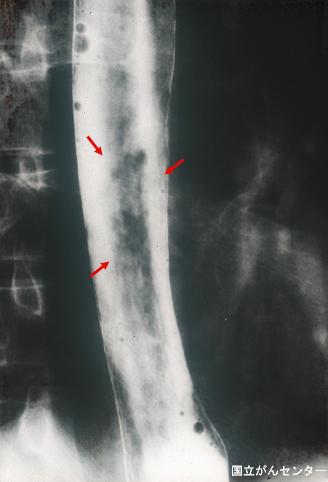

疾患(病理主体)の分類悪性上皮性腫瘍/扁平上皮癌

部位(臓器別)食道/下

検査方法X-P

腫瘍の肉眼分類0型(表在型)/IIc型(IIc)

病変の最大径(ミリ)10〜14

腫瘍の深達度mm

多発腫瘍(同一臓器)有(同時性)